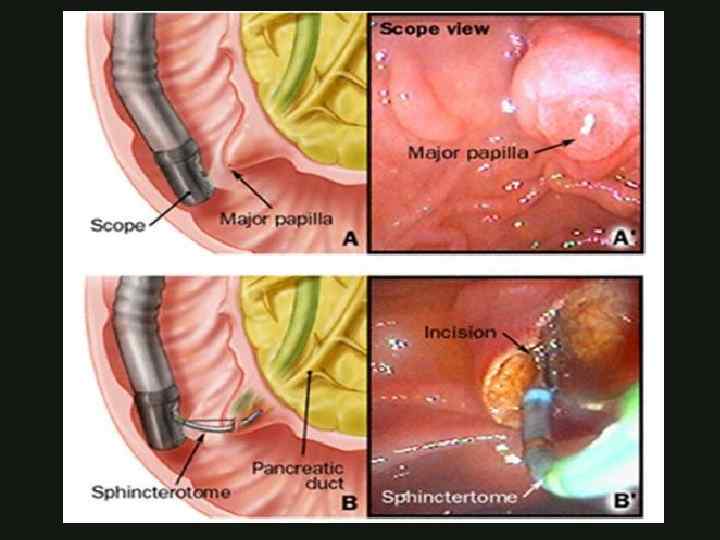

ЭНДОСКОПИЧЕСКОЕ ЛЕЧЕНИЕ ОСТРОГО ОТЕЧНОГО ПАНКРЕАТИТА Эндоскопическая папилосфинктеротомия Эндоскопическое стентирование ЭРХПГ КАФЕДРА ХИРУРГИИ МОСКОВСКОГО ФАКУЛЬТЕТА

ЭНДОСКОПИЧЕСКОЕ ЛЕЧЕНИЕ ОСТРОГО ОТЕЧНОГО ПАНКРЕАТИТА Эндоскопическая папилосфинктеротомия Эндоскопическое стентирование ЭРХПГ КАФЕДРА ХИРУРГИИ МОСКОВСКОГО ФАКУЛЬТЕТА